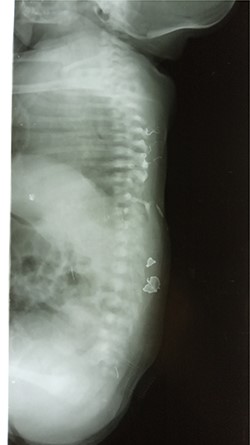

Abdominal X-ray revealed absence of the left 10th to 12th ribs along with half of the 9th rib and a mild lumbar scoliosis (Fig. 2). The shadow of the intestines was seen close to the left abdominal wall. Lateral abdominal X-ray showed a defective ninth hemivertebra (Fig. 3). Abdominal sonography showed absence of muscles of the lateral abdominal wall in the left lumbar region and a lumbar hernia with a diameter of 2.5 cm. Liver, spleen and both kidneys were normal. Laboratorial tests did not raise any suspicions.